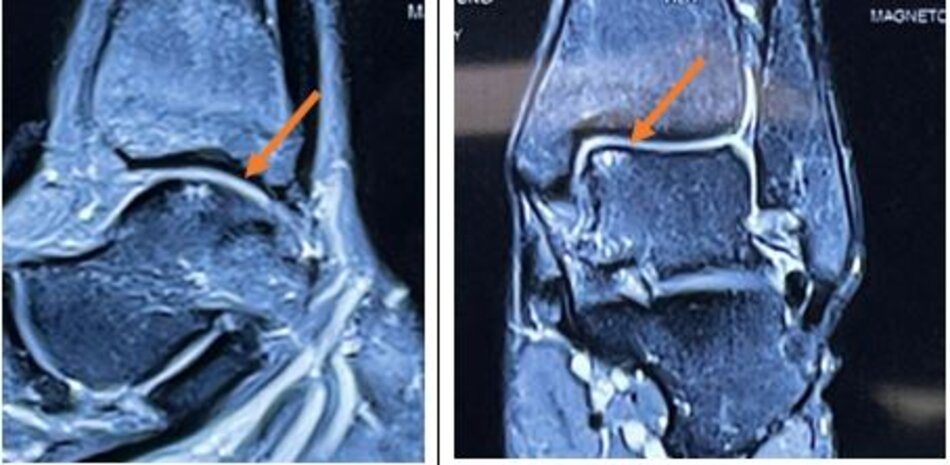

Viêm xương sụn lóc tách

Hình ảnh tổn thương viêm xương sụn lóc tách xương sên trên phim chụp MRI

MRI sau mổ 6 tháng

Viêm xương sụn lóc tách xương sên mức độ nặng có chỉ định ghép xương – sụn từ lồi cầu xương đùi